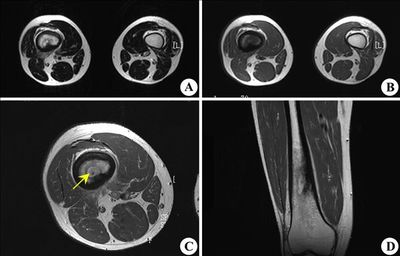

硬化性骨髓炎是一种低毒力感染引起的以髓腔密度增高,闭塞,骨质硬化为特征的慢性骨感染,临床上的检查方法主要是应用X线检查,其表现主要为:

长骨局限性或广泛性骨质增生硬化,皮质增厚,髓腔狭窄闭塞,在骨质破坏区内一般无低密度破坏,但病史较长者可有小的不规则骨质破坏区,骨髓炎以破坏区周边骨质硬化,向正常区逐渐移行,骨内膜增厚,髓腔变窄为特征,有别于肿瘤病变。

发病初期1个月内无异常表现,时间长可见骨皮质弥漫性增厚,致密,呈硬化状,与正常骨无明显分界,骨髓腔较正常狭窄或闭塞,说明髓腔内膜也有增生和新骨形成。

本病的临床特点是骨组织受感染后,由于强烈的成骨反应,而引起骨硬化,没有骨坏死,化脓,亦无死骨形成。多在长管状骨骨干皮质,常见于股骨或胫骨,一侧或两侧骨干皮质呈棱形增厚硬化,严重时,髓腔几乎消失,患肢呈持续性隐痛可逐渐缓解,但易反复发作,全身症状不明显,局部有时无症状,或有肿痛等炎性反应,压痛和胀痛以夜间比白天为剧,病程发展漫长,因外伤或其他疾病可能激发加剧,但关节多数不受影响。